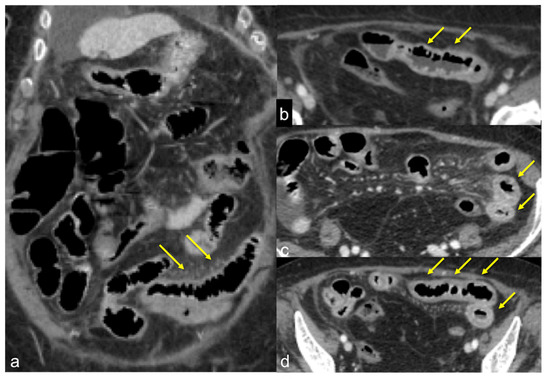

| Colorectal Cancer/Polyps (Figure 6, Figure 36, Figure 37 and Figure 38) | Bowel obstruction with or without bleeding. | Adenocarcinoma: irregular wall thickening with or without stenosis [25]; Polyps: mass-forming protrusions in the intestinal lumen with vascularised peduncle. |

| Inflammatory Bowel Disease (Figure 39 and Figure 40) | Haematochezia-rectorrhagia. | Acute: thickening of the walls, engorgement of the adjacent vasa recta, hyperaemia of the mucosa and infiltration of perirectal fat. Chronic: the colon and rectum are narrowed and shortened, without haustra, and with proliferation of the perirectal fat. |

| Colitis (Figure 41) | It depends on the aetiology. | Non-specific but associated with medical history, the clinical history and location of the lesions, it may be useful for diagnostic purposes. |